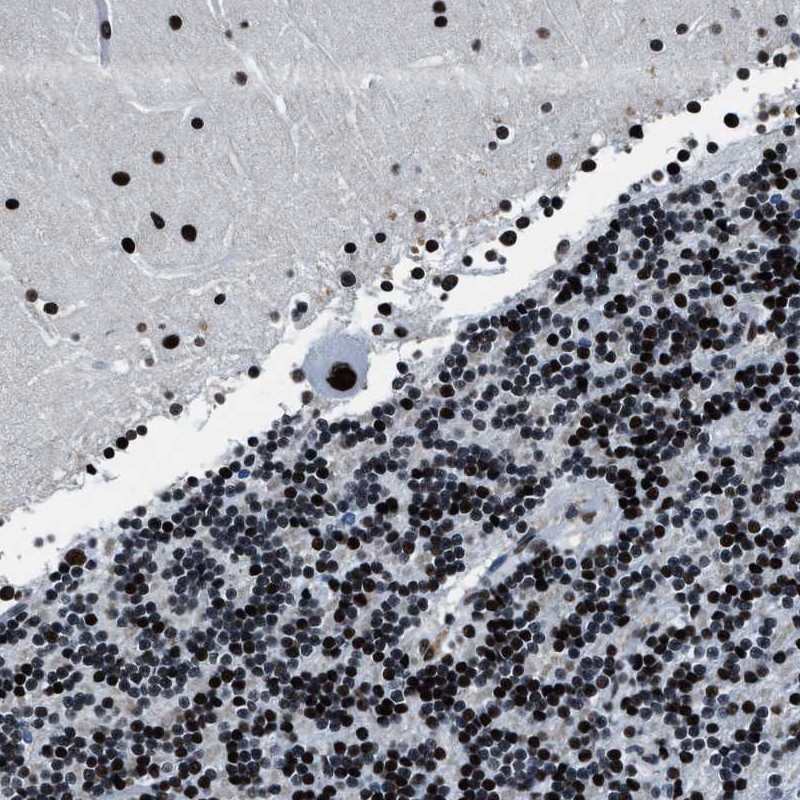

Immunohistochemical staining of human cerebellum shows strong nuclear positivity.